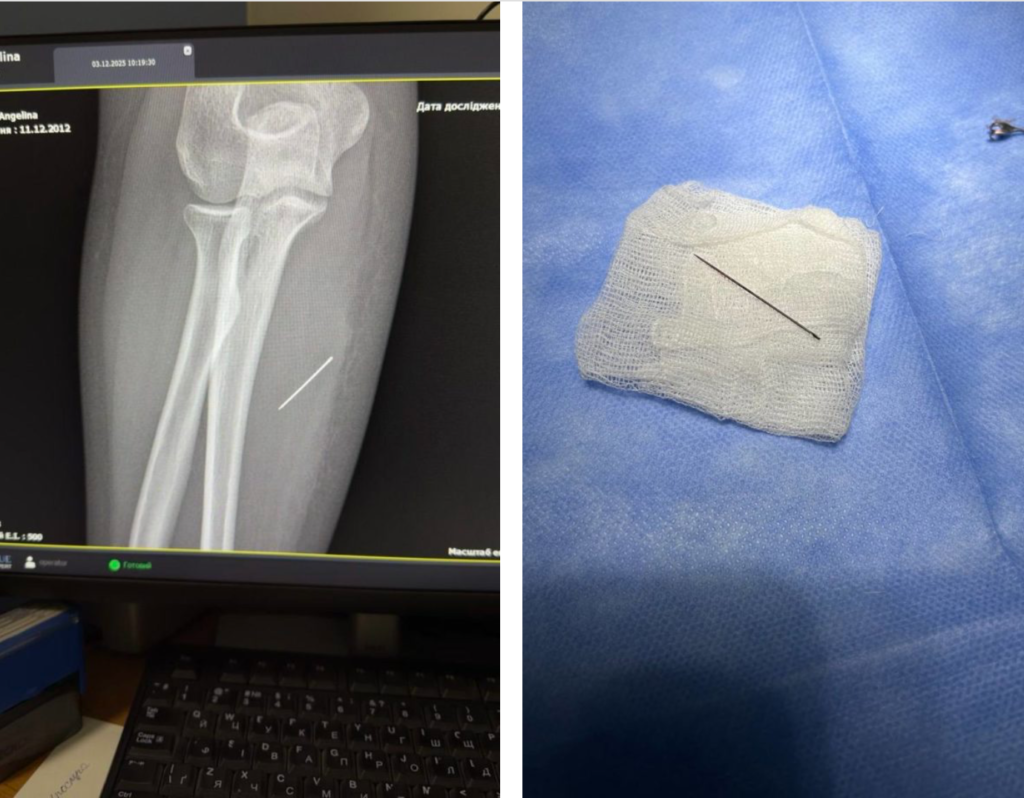

За тиждень голка мігрувала глибше. Рентген показав, що вона зайшла під кутом 45 градусів і застрягла в товщі м’яза. Подальше зміщення могло призвести до ушкодження судин або нервів.

Під час операції лікарям було критично важливо витягнути голку точно за траєкторією входження, аби вона не зламалася. За допомогою рентген-навігації хірурги точно визначили її місце, зробили мінімальний розріз і безпечно вилучили сторонній предмет.